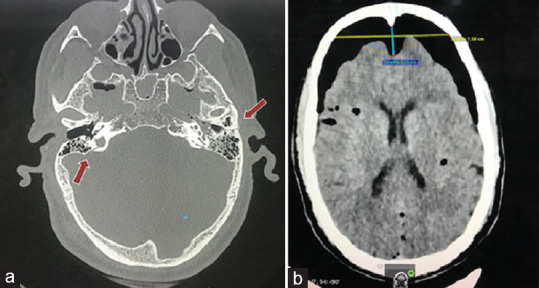

Traumatic pneumocephalus is not an unusual entity. Mostly, such cases are managed according to the patient's neurological status, guided by computed tomography (CT) imaging, and the patient responds well to conservative treatment. However, it seldom progresses to tension pneumocephalus, and if it does along with deterioration of the neurological condition, then neurosurgical intervention becomes necessary. On CT, its appearance is named "Mount Fuji" sign. The most widely documented peril involves increased intracranial pressure causing mass effect and, in some cases, cerebral herniation. However, one unspoken aspect leading to sudden death is seizure. We report the case of a 52-year-old male, admitted after vehicular accident responding well to the conservative treatment along with resolution of tension pneumocephalus. However, he developed generalized tonic-clonic seizures leading to sudden death. Through this case report, we will be discussing the association of pneumocephalus with seizures and seizures leading to sudden death.